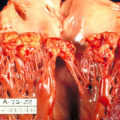

Chronic rheumatic heart disease develops when rheumatic fever-related valve scarring leads to stenosis with the classic fish-mouth appearance.

In chronic rheumatic heart disease, the chordae tendineae and cusps thicken as a result of the mitral valve being involved almost always.

Quite often the aortic valve is involved, which results in the commissures fusing together.